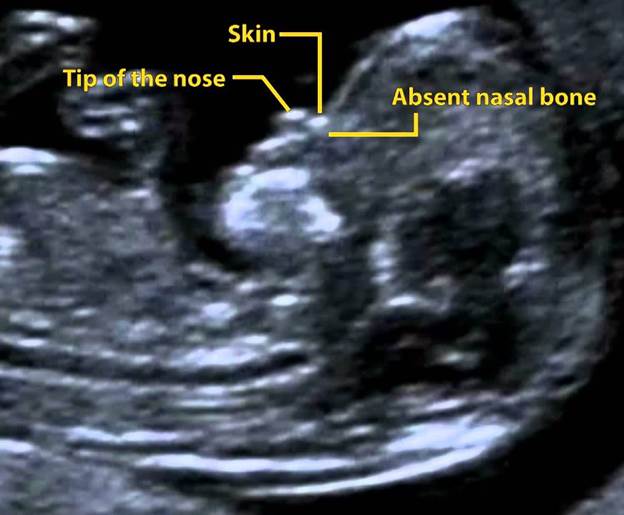

Though the experience is often reassuring, neurosonography can sometimes uncover anomalies. Common abnormalities identifiable include acrania, where the skull is partially missing, and holoprosencephaly, which affects the brain’s structure.